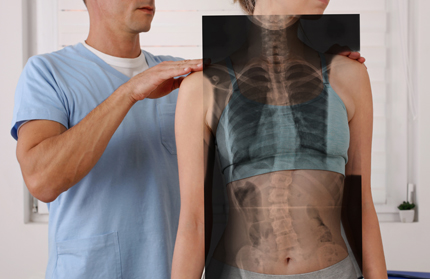

X-Ray Studies

Depending on your specific condition, we may take X-rays as well. X-rays help us develop the most effective treatment plan for you, and alert us of any serious spinal conditions. Most people are amazed once they see their X-rays up close. In some cases, they can even identify their misalignments and degeneration themselves.